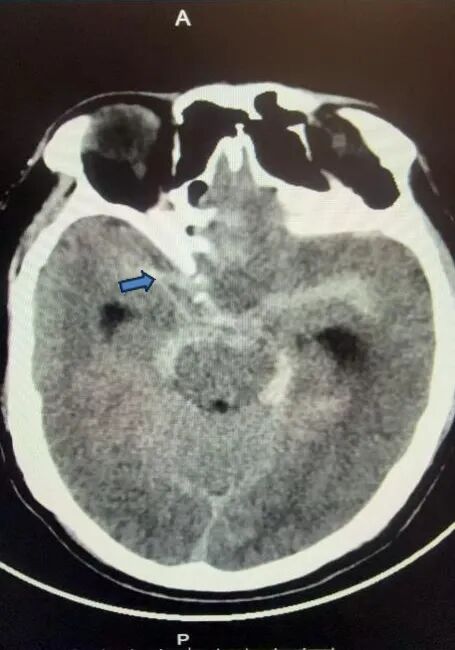

一位63岁的男性,因“突发头颈部疼痛2小时”入院。入院查体:轻度意识障碍,头颅CT检查提示颅内蛛网膜下腔出血,头颈部血管CTA检查未见明显异常。经神经外科团队科内讨论后仍不排除患者存在脑血管病变可能,遂行全脑脑血管造影术,术中发现存在前颅底硬脑膜动静脉瘘,眼动脉供血,经海绵窦、岩下窦向颈内静脉引流。